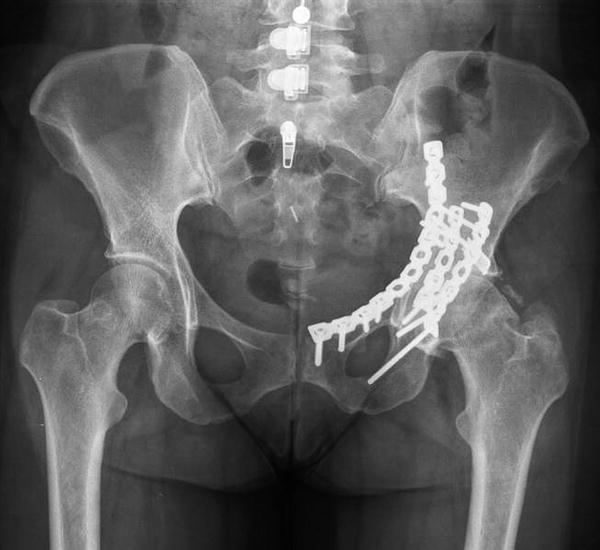

Similar to the hip and knee, this is also called a “wear and tear” type of arthritis, and probably occurs as some combination of use. It is a type of osteoarthritis. Post traumatic arthritis this condition is very similar to osteoarthritis, but the onset is secondary to a traumatic event that initiates damage to the cartilage surface.

Typically the arthritis sets in directly after a major surgery or even a minor surgery, like to the hand. If symptoms persist after six months, it’s categorized as chronic pta, resulting in chronic osteoarthritis or inflammatory arthritis [ 4 ]. Pta causes about 12% of all osteoarthritis cases, and a history of physical trauma may also be found in patients with chronic inflammatory arthritis.

This event can be a traumatic shoulder dislocation, a severe fall onto the shoulder, or a fracture. To suppress the natural tendency of most patients to immobilize the painful joint until comfort returns. Although this type of arthritis is triggered by physical trauma that damages a joints cartilage or bone, the condition itself is actually a form of osteoarthritis.

Avascular necrosis (avn) avascular necrosis can result in shoulder arthritis by destroying the bone and the joint tissues in your shoulder. Shoulder injuries are common due to the instability of the hinge joint and a fracture or shoulder dislocation can trigger the onset of posttraumatic arthritis. It occurs when the cartilage in the injured joint wears out as a result of the physical trauma.